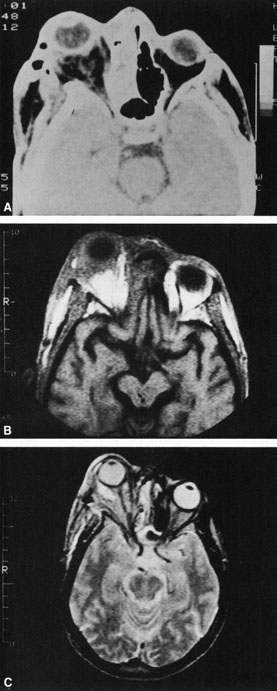

CT shows sinusitis with or without bone destruction and is indistinguishable from other causes of orbital cellulitis.128 MRI may show carotid narrowing, occlusion, and absent flow in the superior ophthalmic vein (Fig. 24).72

Fig. 24. Mucormycosis. A. A 72-year-old patient with acute myelogenous leukemia and invasive fungal sinusitis presented with orbital cellulitis. B. Involvement of hard palate with eschar. C. Fungi in the posterior ciliary artery.

Diagnosis is made by having a large index of suspicion and obtaining specimens of nasal turbinate, sinus, or infected orbital tissue. Large, branching nonseptate hyphae are readily apparent on hematoxylin and eosin staining or with methenamine silver staining (see Fig. 23). These hyphae can be grown on fungal culture.